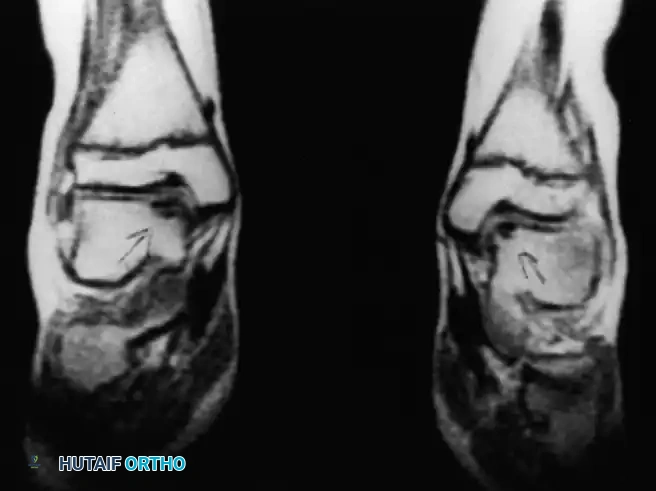

* Anterolateral Lesions: Caused by inversion and dorsiflexion. The talar dome impacts the fibula, creating a shallow, wafer-shaped shear fracture. These are almost exclusively traumatic and are more likely to become symptomatic and displaced.

* Posteromedial Lesions: Caused by inversion and plantarflexion. The talar dome impacts the tibial plafond, creating a deep, cup-shaped compression fracture. These can be asymptomatic for years and may have a genetic or ischemic component.

Fig. 13: MRI and corresponding arthroscopic view of a classic posteromedial osteochondral lesion of the talus.